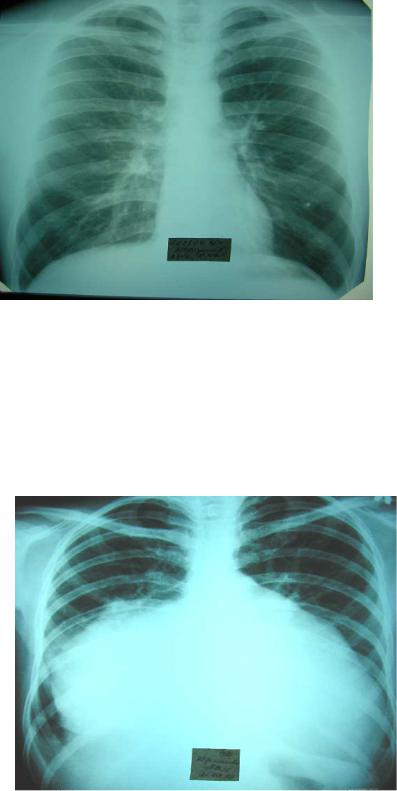

Fig.13"Spherical” configuration of the heart. in a patient with a congenital heart defect. The chest radiograph of a patient with a ventricular septal defect (direct view): the shadow of the heart increased at the expense of both ventricles, visible bulging arc pulmonary trunk (arrow), pulmonary picture in the basal parts of the lungs are strengthened.

"Drip" configuration of the heart - the left and right border of cardiac dullness is shifted medially, the area of cardiac dullness is diminished, the heart becomes "drip" form, cause - emphysema of the lungs (Fig.14).

Fig.14. "Drip" configuration of the heart